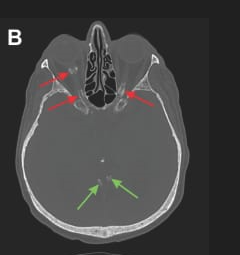

CT (brain window) red arrows show optic nerve sheath calcifications; green arrows show normal posterior fossa.

CT (bone window) – red arrows highlight optic sheath calcifications; green arrows show normal brain tissue.